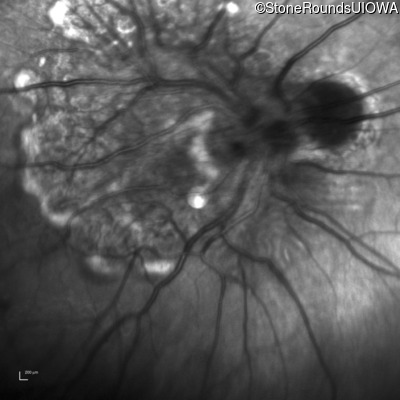

This 9 year old male was noted to have some crossing of his eyes at 2 months of age and the eye exam which followed identified a retinal lesion in the right eye. When he was six years old an epiretinal membrane was noted in his left eye. Two years later it was decided that it was a thin hamartoma in that eye as well. He underwent neuroimaging at age 7 which identified bilateral acoustic neuromas.